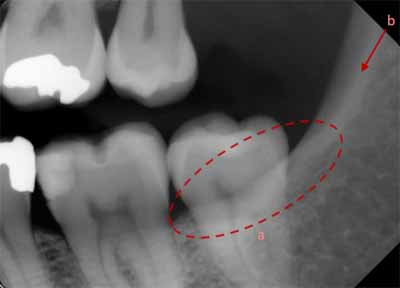

下顎の外側部に向かって後方に移動すると、犬歯、小臼歯、大臼歯が見えます。小臼歯と大臼歯の下には下顎管があり、薄いエックス線不透過性の境界に囲まれた幅広いエックス線透過性の線として現れます。下顎管は下顎の頬側表面にあるオトガイ孔に開口しています。口腔内画像では、オトガイ孔は小臼歯の根尖のすぐ下またはその高さにある丸いエックス線透過性の構造として確認できます(画像 18 および 19 を参照) 。下顎管は下顎枝にあるオトガイ孔から下顎孔まで下顎の外側部分全体に沿って走っています。多くの場合、臼歯の根尖のすぐ下か、同じ高さに位置します。等角投影と軸測投影の両方で、臼歯の頂点に重なって描かれることもあります(画像20と21を参照)。